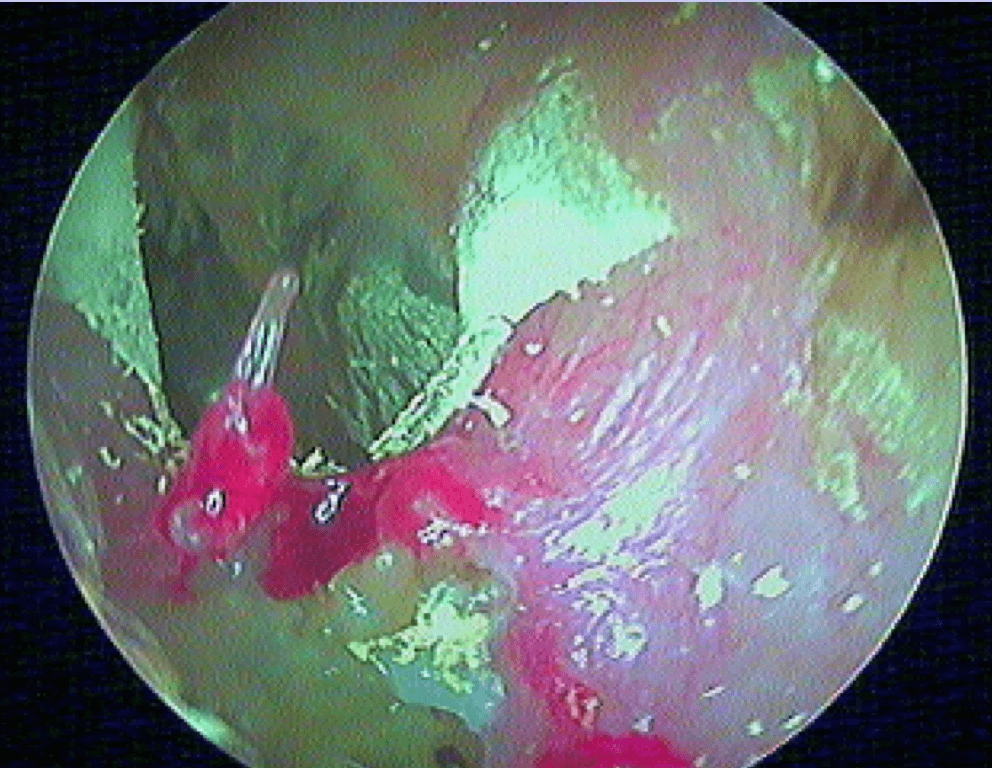

Pour comprendre la paracentèse, ici au laser diode sous A/L au cabinet:

Et la mise en place d'aérateur de type T-tube ici: